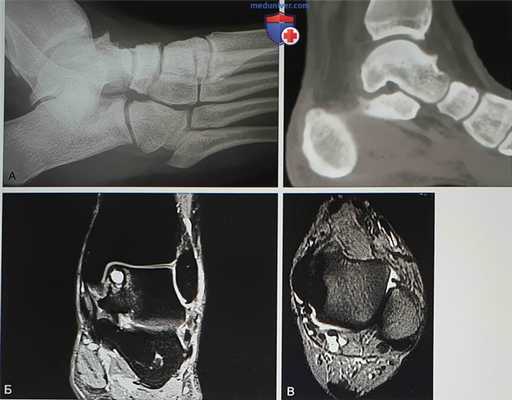

Рисунок 1

- На рентгенограммах с нагрузкой в боковой проекции могут быть видны остеофиты большеберцовой и таранной костей. В переднем завороте могут быть свободные суставные тела, могут быть признаки перелома остеофитов (рис. 1, А):

• Магнитно-резонансная томография (МРТ) позволяет увидеть выпот в переднем отделе голеностопного сустава, синовит, а также остеофиты (рис. 1, Б). Может быть видна гипертрофированная связка Бассетта (рис. 1, В)

• В голеностопном суставе могут определяться остеохондральные кисты и хондральные повреждения, свидетельствующие о более выраженных изменениях, ухудшающих долговременный прогноз

- Компьютерная томография позволяет оценить размеры и локализацию остеофитов, что может оказывать влияние на выбор артроскопических портов. Также КТ позволит увидеть субхондральные кисты и участки склероза в голеностопном, а также в смежных суставах